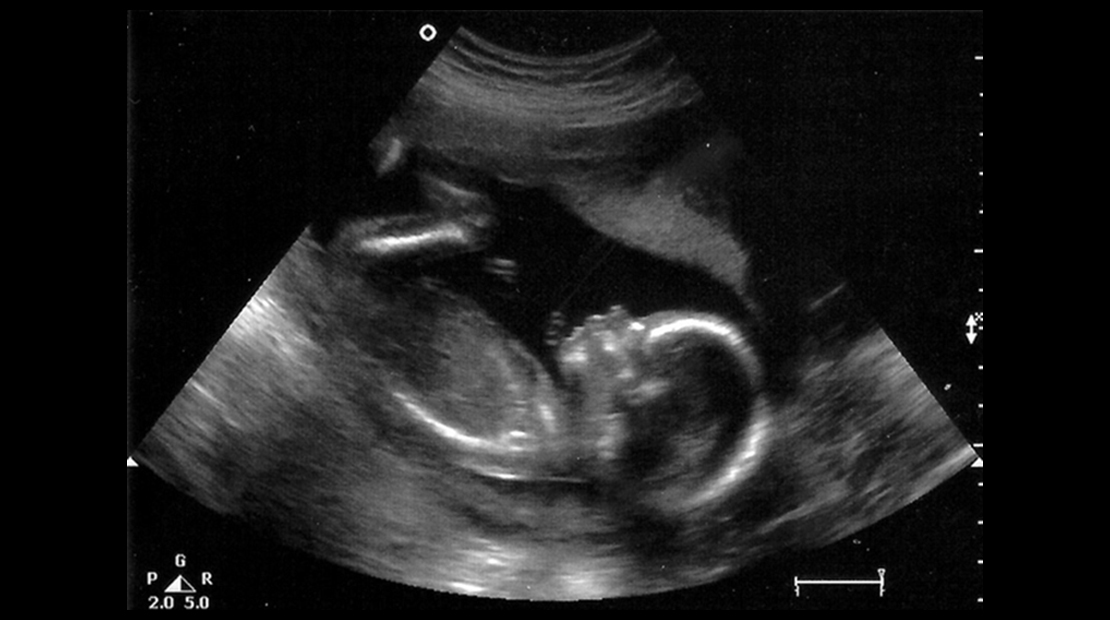

Важный этап: развитие малыша на 20-й неделе беременности

Раздел: Снимки-откровения